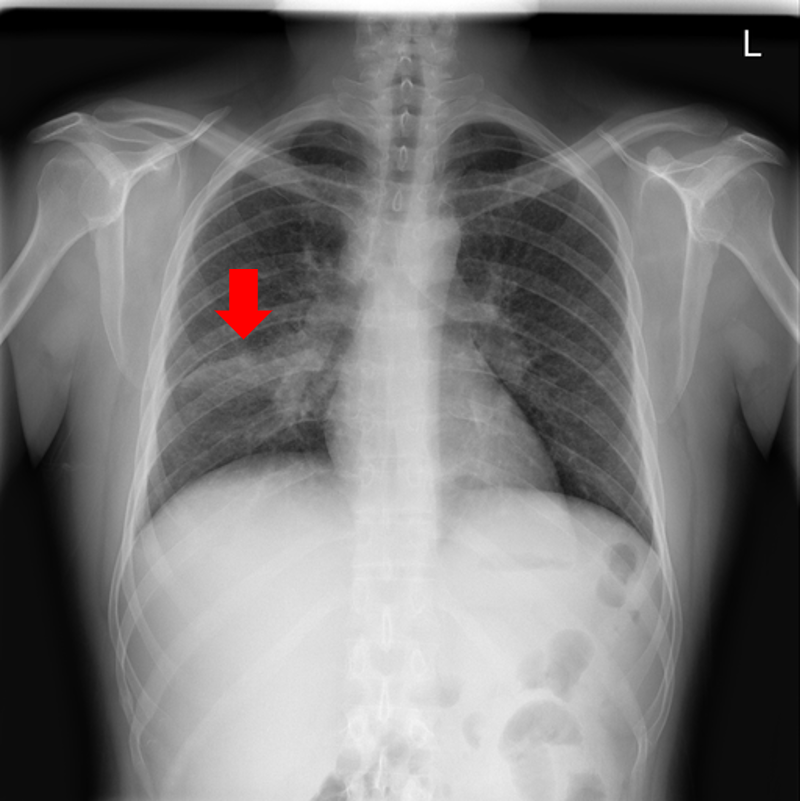

Refer to caption

Figure 9: Typical CXRs with pneumonia-like lung opacity from among the top 1,000 CXRs most likely to have an abnormality according to the logarithm posterior probability out of the 13,863 abnormal CXRs. The lesion is indicated with a red arrow if applicable.

Figure 9 shows CXRs suggested to have pneumonia-like lung opacity with the logarithm posterior probability. These CXRs are the top 1,000 CXRs most likely to have an abnormality out of the 13,863 abnormal CXRs.